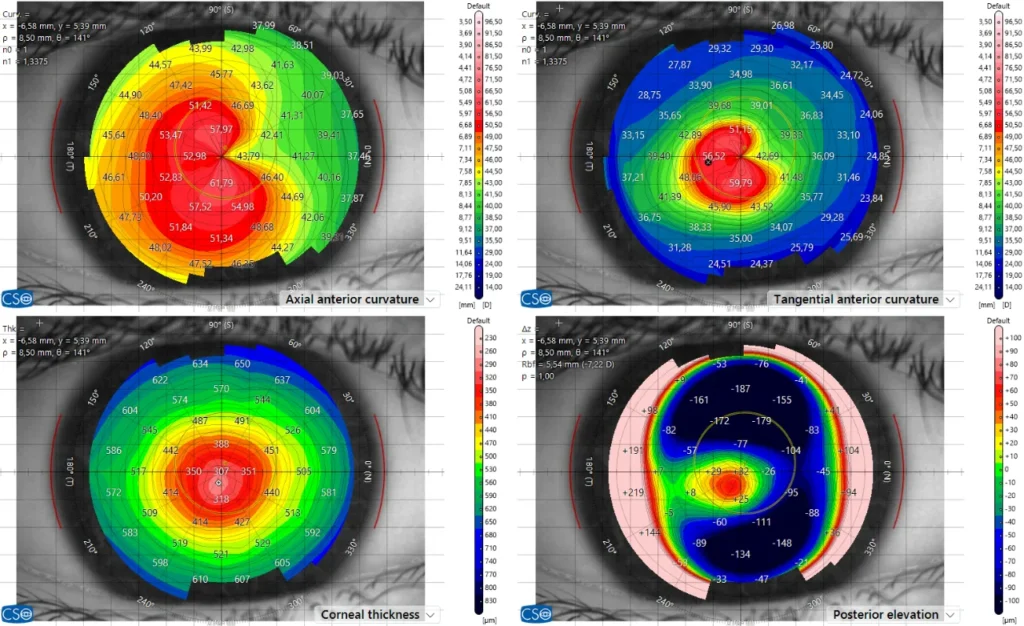

Die Pentacam erfasst mit einer rotierenden Kamera ein 3D-Bild Ihrer Hornhaut und misst ihre Form und Dicke an Tausenden von Punkten. So können wir Keratokonus in einem sehr frühen Stadium erkennen - auch wenn die Sehkraft noch normal erscheint.

Das MS-39 kombiniert Hornhauttopographie mit hochauflösender OCT (optische Kohärenztomographie). Es liefert uns ein extrem detailliertes Bild der Hornhautschichten, mit dem wir subtile strukturelle Veränderungen erkennen und ein Fortschreiten im Laufe der Zeit überwachen können.

Dank neuester Technologien sind wir heute in der Lage, sowohl die vordere als auch die hintere Oberfläche der Hornhaut mit extrem hoher Präzision zu messen. Dank dieser verbesserten Genauigkeit können Anomalien bereits in sehr frühen Stadien erkannt werden, was zu schnelleren und zuverlässigeren Diagnosen führt. Erkrankungen wie Keratokonus oder Pellucid Marginal Degeneration (PMD) lassen sich nun deutlich früher als bisher diagnostizieren, was die Patientenergebnisse verbessert und eine rechtzeitige Behandlung ermöglicht.

Diese Hornhaut ist erkrankt und benötigt weitere Untersuchungen/Behandlungen. Man erkennt, dass die Hornhaut im oberen Anteil flach ist und im unteren Anteil sehr stark vorgewölbt. Die Sehkraft ist verzerrt, es bestehen Doppel- oder sogar Dreifach- und Vierfach-Bilder und in vielen Fällen kann auch eine Brille die Sehschärfe nicht mehr wiederherstellen. Zudem ist die Krankheit fortschreitend und kann vor allem bei Kindern und Jugendlichen bis zu schwersten Sehbehinderungen führen.